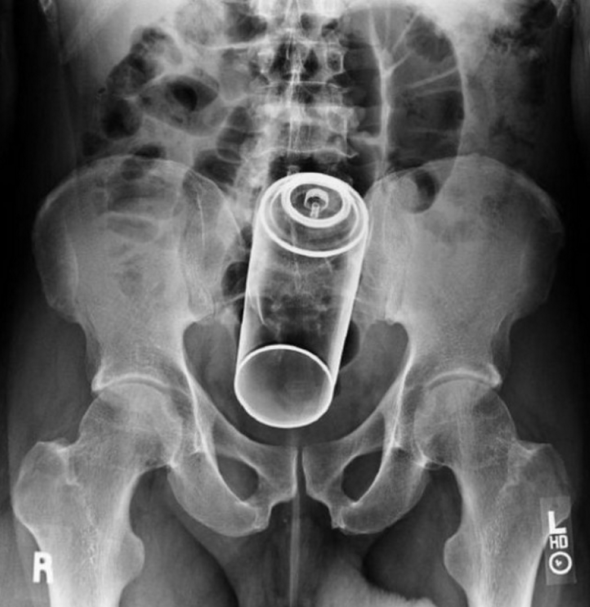

6. 5. Sprej

Tento člověk asi neměl nic jiného po ruce a přišlo to na něj znenadání. Strkat si dobrovolně do těla sprej, může snad jen úplný hlupák. Kdyby začal vytékat nebo praskl, tak by to asi bylo hodně nepříjemné a člověka by to mohlo i zabít. Lidé často k lékařům chodí i s velmi podivnými historkami, proč vlastně mají v konečníku či vagíně ten dotyčný předmět a jak se jim tam dostal. U některých vysvětlení byste dostali záchvat smíchu.